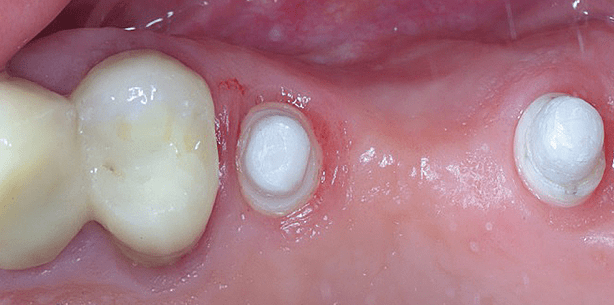

Position 15 zeigte eine gute Knochenqualität (D2) und ein Z5m Zirkolith® Monotype Implantat (Durchmesser 4 mm, Länge 10 mm) von Z-Systems wurde mit einem Torque-Wert von 45 Ncm inseriert. An Position 17 stellte sich eine deutlich schlechtere Knochenqualität (D3) dar, die eine erfolgreiche Insertion eines einteiligen Implantates mit einem zu erreichenden Torque von mindestens 45 Ncm auch bei unterdimensionierter Aufbereitung ­infrage stellte.

Aufgrund des gleichen OP-Protokolls für das zweiteilige Z5c Zirkolith® Keramikimplantat von Z-Systems konnte intraoperationem auf die Insertion eines zweiteiligen Keramikimplantats umentschieden werden. Es wurde ein Z5c Zirkolith® zweiteiliges Implantat (Durchmesser 4 mm, Länge 10 mm) von Z-Systems mit einem Torque-Wert von 25 Ncm inseriert. Die provisorische Sofortversorgung erfolgte nun über die Zähne 13, 14 und Implantat 15. Für den Osseointegrationsprozess sind Mikrobewegungen zwischen 50 bis zu 100 Mikron im Sinne eines Knochentrainings von Vorteil. ­Makrobewegungen über 100 Mikron sind zu vermeiden. Aus diesem Grund wurde die statische Okklusion in Regio 15 reduziert und auf dynamische Okklusion im Bereich 14 bis 15 verzichtet.